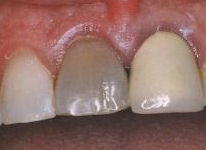

- Αποχρωματισμός του δοντιού (ο νεκρός ιστός του πολφού σκουραίνει το χρώμα του δοντιού)